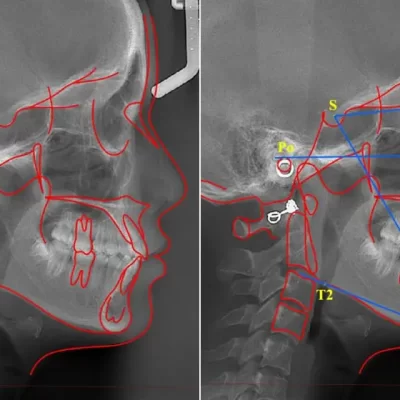

培训日期: 2026-03-06 视频内容:介绍了软件版本eSet4.01的升级内容,主要介绍了新增的核心功能——非节点分布算法。视频详细讲解了如何使用新算法进行牙齿移动路径的设计,包括选择分布算法、...